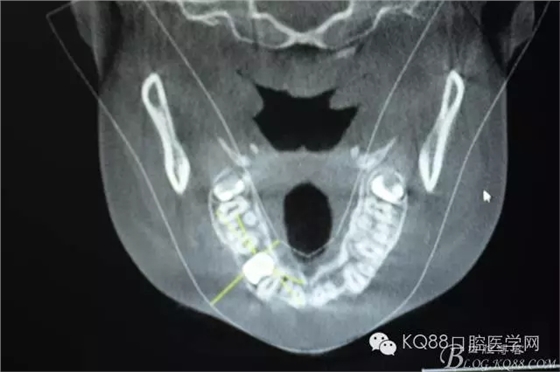

圖5.水平剖面觀:14牙冠緊鄰15與13牙根之間,要求分牙一定要小心謹慎